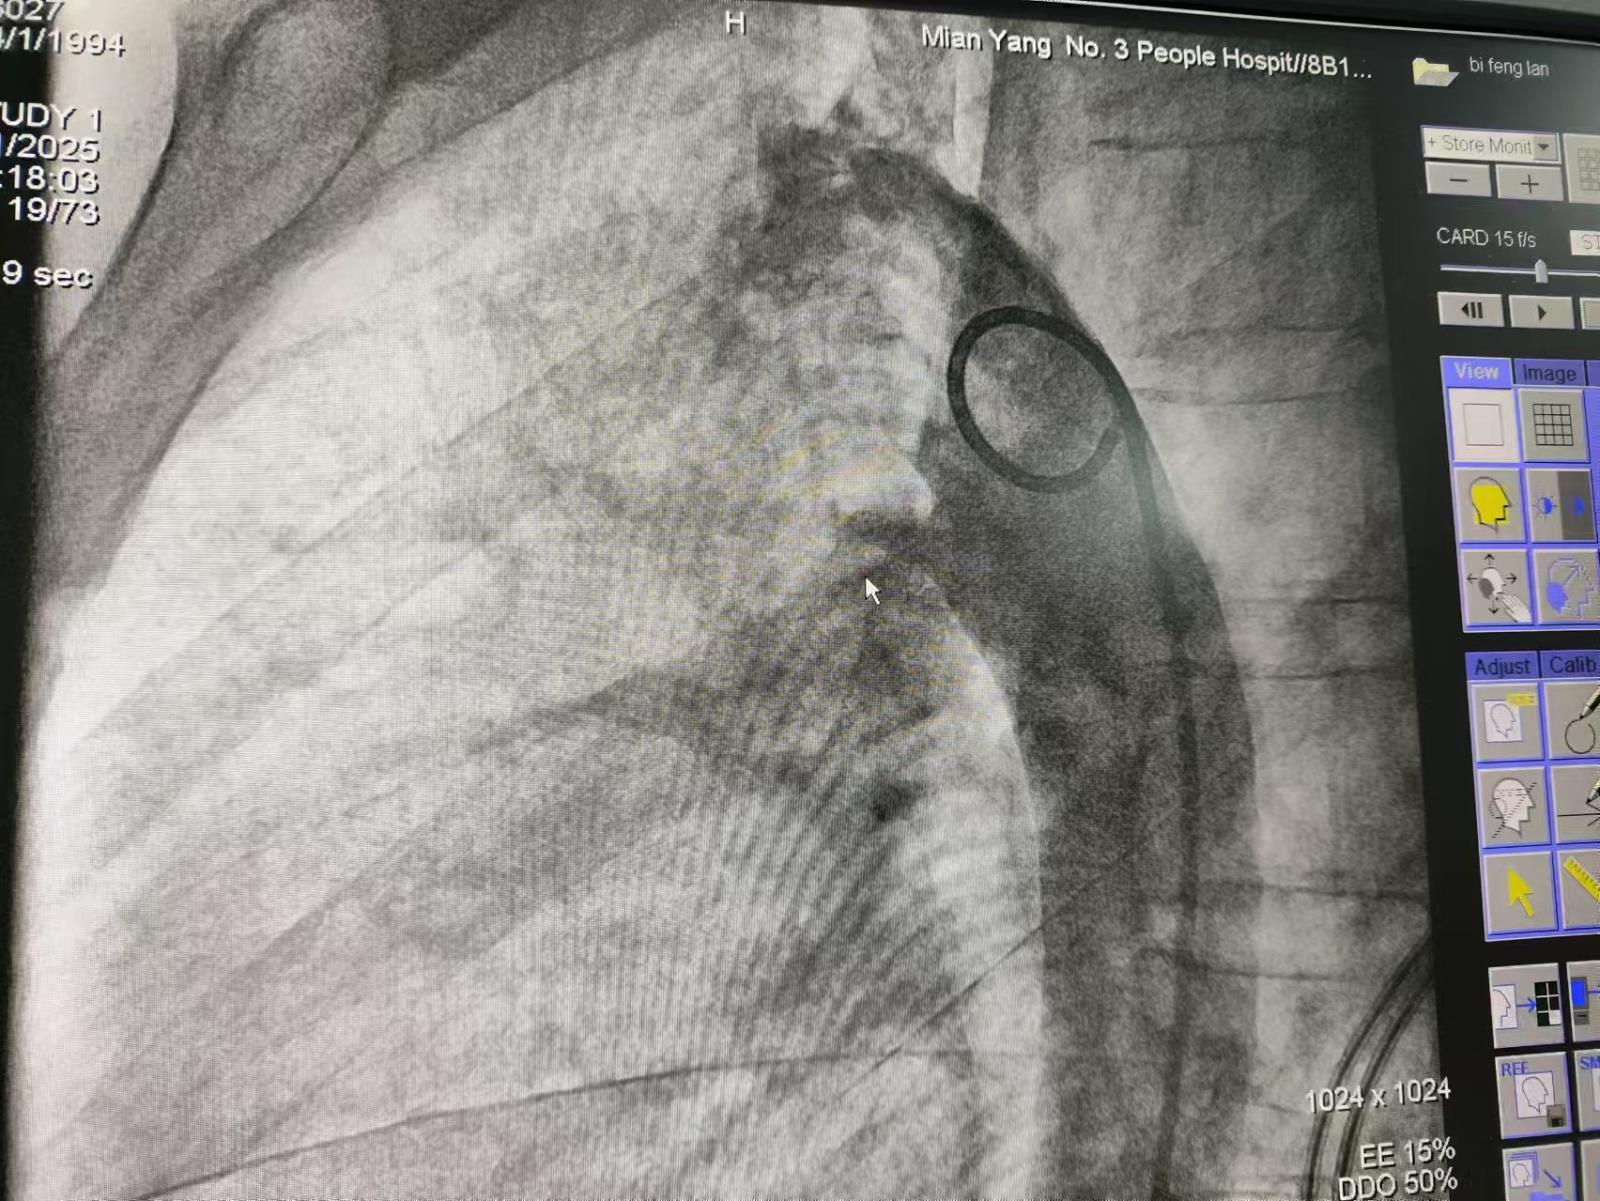

手术医生唐波、沈松林、童健文默契配合,在对患者施行局麻并皮肤消毒后,术中用Seldinger技术,用刀片尖挑开穿刺点处皮肤仅仅约2mm小口,选择合适的含针芯穿刺针对患者双侧的股动脉、股静脉分别进行穿刺,拔出针芯后立即插入导丝并退出穿刺针,通过导丝引入扩张鞘管及猪尾巴造影导管进入主动脉时,快速注入造影剂。X线电影下清晰可见,造影剂从主动脉经未闭的动脉导管向肺动脉分流,形成"喷射征",该患者导管的形态为主动脉端粗、肺动脉端细的漏斗型。

利用介入诊疗中心的大型C臂对动脉导管定量测量:精确测量导管直径及长度、主动脉端至肺动脉端距离,为封堵器尺寸的选择提供科学精准的依据。

医生再在动脉侧送入导丝,静脉侧顺血管通路放入VER建立静脉侧通道,送入抓捕器抓捕主动脉侧通路的导丝,建立主动脉-肺动脉之间的动脉-静脉轨道。顺轨道将VER通过未闭的动脉导管,释放封堵器。封堵后重复造影确认: 封堵器完全覆盖导管开口,无造影剂渗漏,无残余分流。封堵器的腰部完全卡在导管最窄处,盘片紧贴主动脉/肺动脉壁。以确保封堵器的释放成功。肺动脉显影延迟,主动脉弓形态恢复,介入术取得圆满成功。